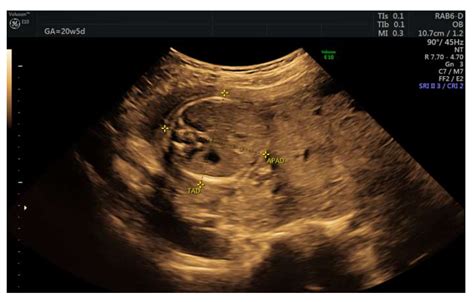

Diagnosing a partial molar pregnancy usually involves a combination of ultrasound imaging and laboratory testing. Since physical symptoms can be misleading, medical professionals rely on concrete data:

Ultrasound Abnormal placental tissue or a fetus with severe structural abnormalities.

• partial molar pregnancy on ultrasound

• partial molar pregnancy ultrasound images